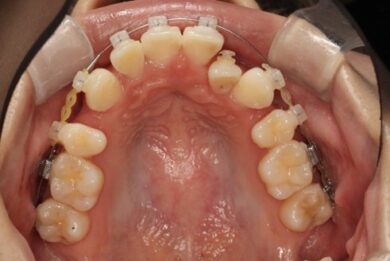

上顎のビフォアアフター

抜歯して空いたスペースが少しずつ埋まってきているのが分かりますね。

2か月前 現在

上顎の方は左の前から2番目の歯が入るスペースを確保するために、3番目の犬歯を奥の方(後ろ)に下げていきます。

右側も同様、全体を奥の方(後ろ)に下げていきます。

左の2番目の歯が前方に出てくるためにはスペース確保が必要です。歯と歯の間を広げてスペースができたらやっとブラケットが付けられます。